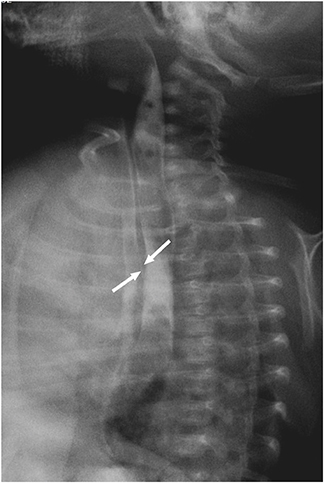

A male full-term neonate presented to emergency room with cyanosis after breastfeeding. The patient was delivered by planned caesarian section 12 hours before arrival. Chest radiograph taken on the first day of life was cleaned but the radiograph taken on the third day of life suggested aspiration pneumonitis (

Fig. 1). Upper gastrointestinal (GI) series showed gastroesophageal regurgitation with pulmonary aspiration but esophagoscopy and video esophagogram on the eleventh day of life showed no abnormality. Contrast esophagogram was followed on the 33

Fig. 1 Two days after birth (right), chest radiograph shows aspiration pneumonitis which was absent on the date of birth (left).

Fig. 2 H-type tracheoesophageal fistula at 1 cm above the carina (white arrows).